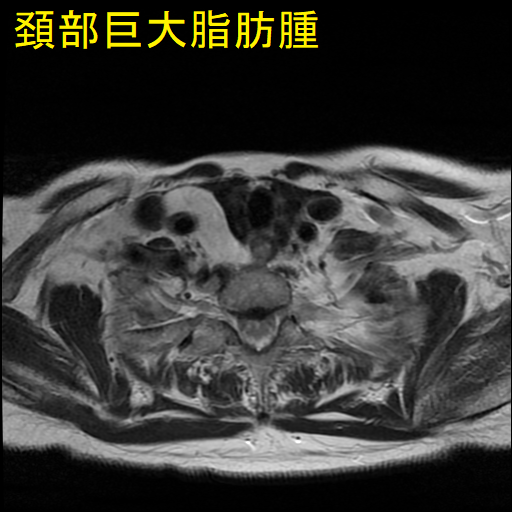

巨大頚部脂肪腫

血管脂肪腫は脂肪腫の一種で脂肪と血管を含みます。20歳から30歳までの若年成人に発症し、その原因として、

ほとんどが前腕ですが、頚部に現れる場合もあります。痛みを伴う点が脂肪腫と異なり、脂肪肉腫とも鑑別を要します。[Skeletal Radiol. 2023 Mar;52(3):541-552.]